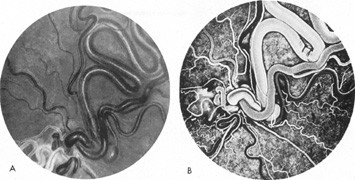

SUPRATENTORIAL

From 85% to 90% of AVMs are in the supratentorial compartment and are supplied primarily by the carotid circulation (Figs. 7 and 8). The remainder are supplied by the vertebrobasilar system. The approximate frequency of location is as follows: frontal, 22%; temporal, 18%; parietal, 27%; occipital, 5%; and deep intraventricular or paraventricular, 18%. The intracerebral site of the malformation does not necessarily indicate that there will be signs referable to that area simply from the mass effect of the malformation. Clinical features primarily result from subarachnoid hemorrhage or intraparenchymal hemorrhage with hematoma formation.

Fig. 7. Supratentorial arteriovenous malformation in a 28-year-old woman with a history of focal motor seizures for many years and a recent subarachnoid hemorrhage. A: Lateral projection carotid arteriogram demonstrating a huge deep hemispheral arteriovenous malformation. B: Frontal projection. C: Fundus photograph showing anomalous tortuous vasculature in each eye. No retinal arteriovenous shunt was detectable.

Fig. 8. Multiple supratentorial arteriovenous malformations (AVMs). A: Lateral projection of left carotid arteriogram shows dilated afferent artery (solid arrow) feeding the right hemispheric parietal AVM (open arrow). B: Right carotid injection fills a second, more posteriorly located, parietooccipital AVM (open arrow), which drains immediately to markedly dilated cortical veins (curved arrow).